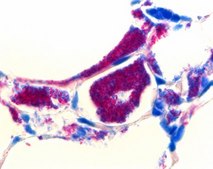

Hydrochloric acid in ethanol - for microscopy, is used for human-medical cell diagnosis and serves the purpose of the bacteriological and histological investigation of sample material of human origin. Acid-fast bacteria are difficult to stain because of the high proportion of lipid and wax in their cell walls. The most efficient staining method is the hot staining according to Ziehl-Neelsen. In this method, carbolfuchsin solution is applied to the specimen and heated. This heating process accelerates the rate at which the fuchsin dye is absorbed and thus also that of the formation of the mycolatefuchsin complex in the cell wall. With the Kinyoun method, a modification of the AFB-Color carbol fuchsin solution renders heating unnecessary (cold staining). Once the acid-fast bacteria have absorbed the fuchsin dye, it is virtually impossible to decolorize them again, even when they are intensively treated with a decolorizing solution such as e. g. hydrochloric acid in ethanol (Product number 1.00327). Accordingly, acid-fast bacteria are termed as acid- and alcohol-fast for staining, and are stained red in the microscopic visualization. Correspondingly, all non-acid-fast microorganisms are counterstained with an appropriate dye. In this instruction for use malachite green is used for counterstaining.

For microscopy. Ziehl-Neelsen staining